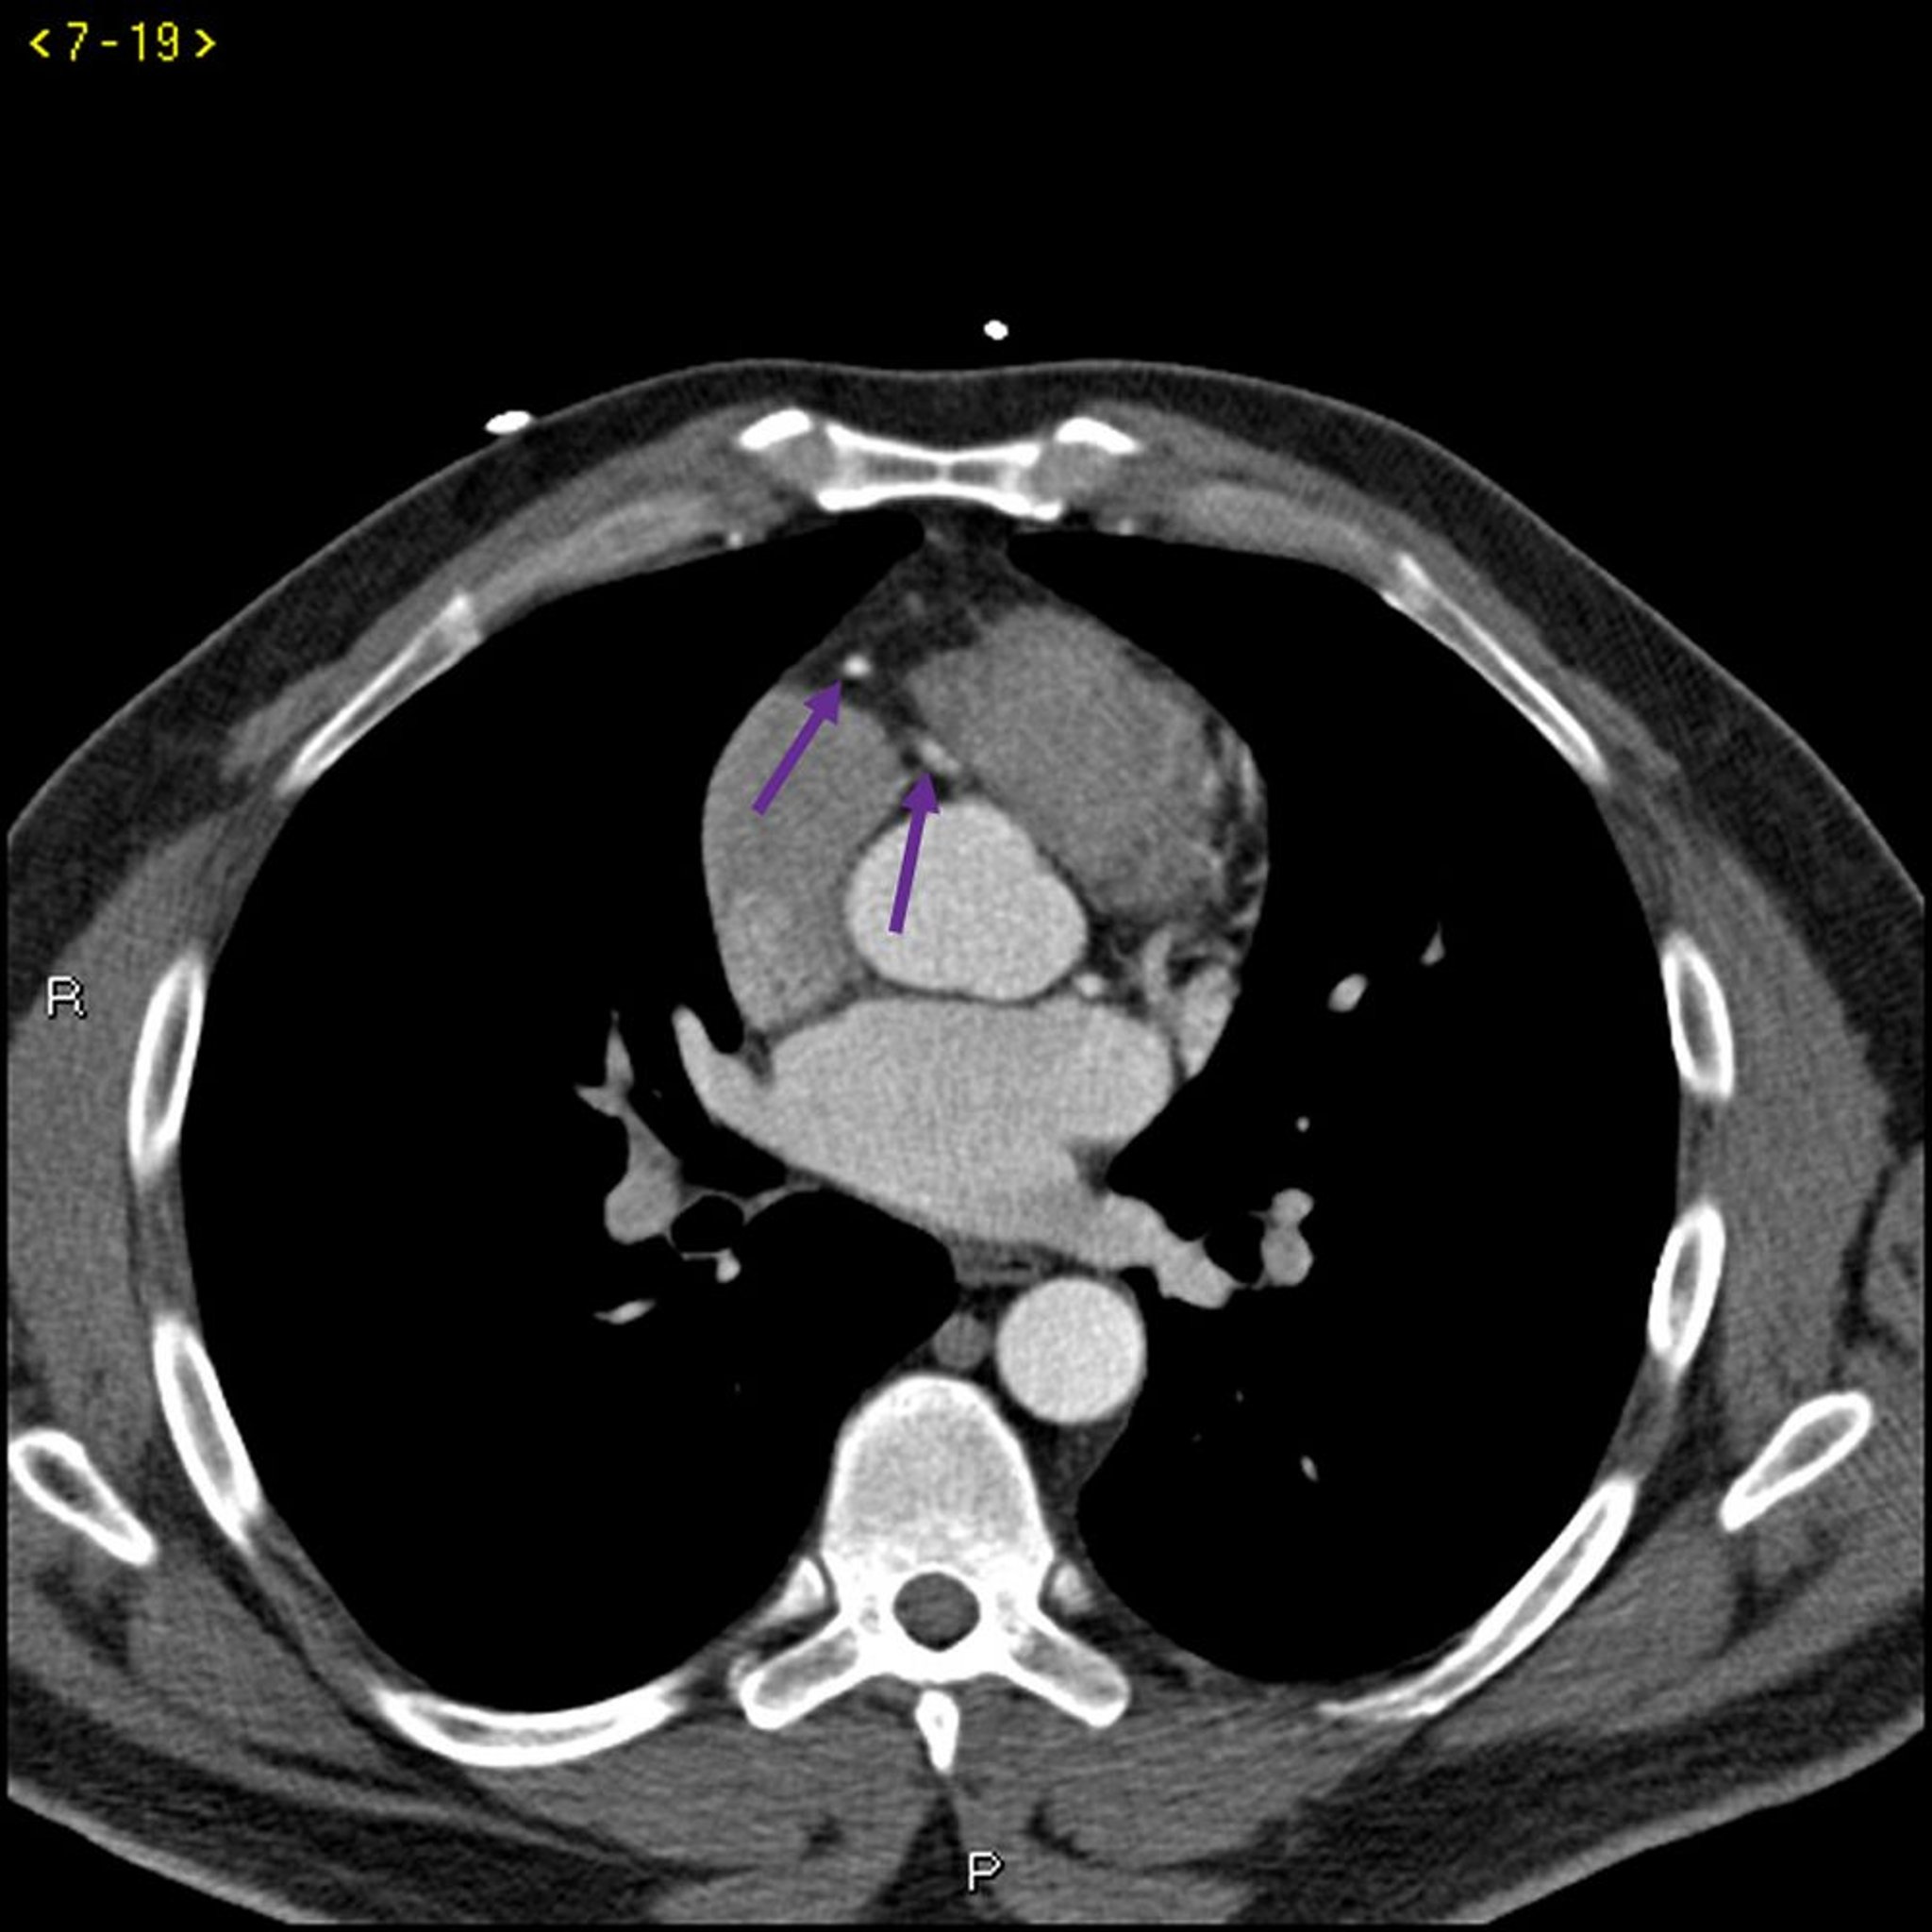

Contrast CT Showing Normal Coronary Arteries – Slide 4

This contrast CT shows normal coronary arteries. The left main is indicated by the red arrow. The left anterior descending and left circumflex arteries are indicated by the green and blue arrows respectively and the right coronary artery is indicated by the purple arrow.